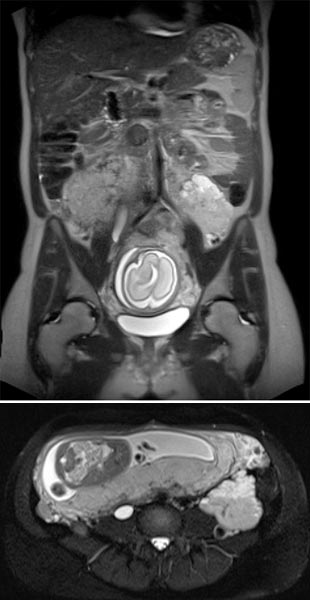

Koronare (oben) und axiale (unten) T2-gewichtete, fettunterdrückte Haste-Sequenzen ohne Kontrastmittel bei der Erstuntersuchung vor der Schwangerschaft.

Koronare (oben) und axiale (unten) T2-gewichtete Haste-Sequenzen ohne Kontrastmittel in der 21. Schwangerschaftswoche.

Während der Schwangerschaft deutliche Größenzunahme der VM, die ventral des linken Musculus posas als signalintense Läsion zur Darstellung kommt, ohne Verdrängung oder Kompression der Plazenta.

Koronare native T2-Haste-Sequenzen zur Verlaufsbeurteilung der VM ventral auf dem linken Musculus psoas aufsitzend in der 21. Schwangerschaftswoche. Während der Gravidität entwickelt die Patientin auch eine Harnstauungsniere Grad III rechts.

In der axialen T2-HASTE-Sequenz in der 21. Schwangerschaftswoche grenzt die VM an die Plazenta, ohne Verdrängung oder Verlagerung von Uterus oder des Fötus.